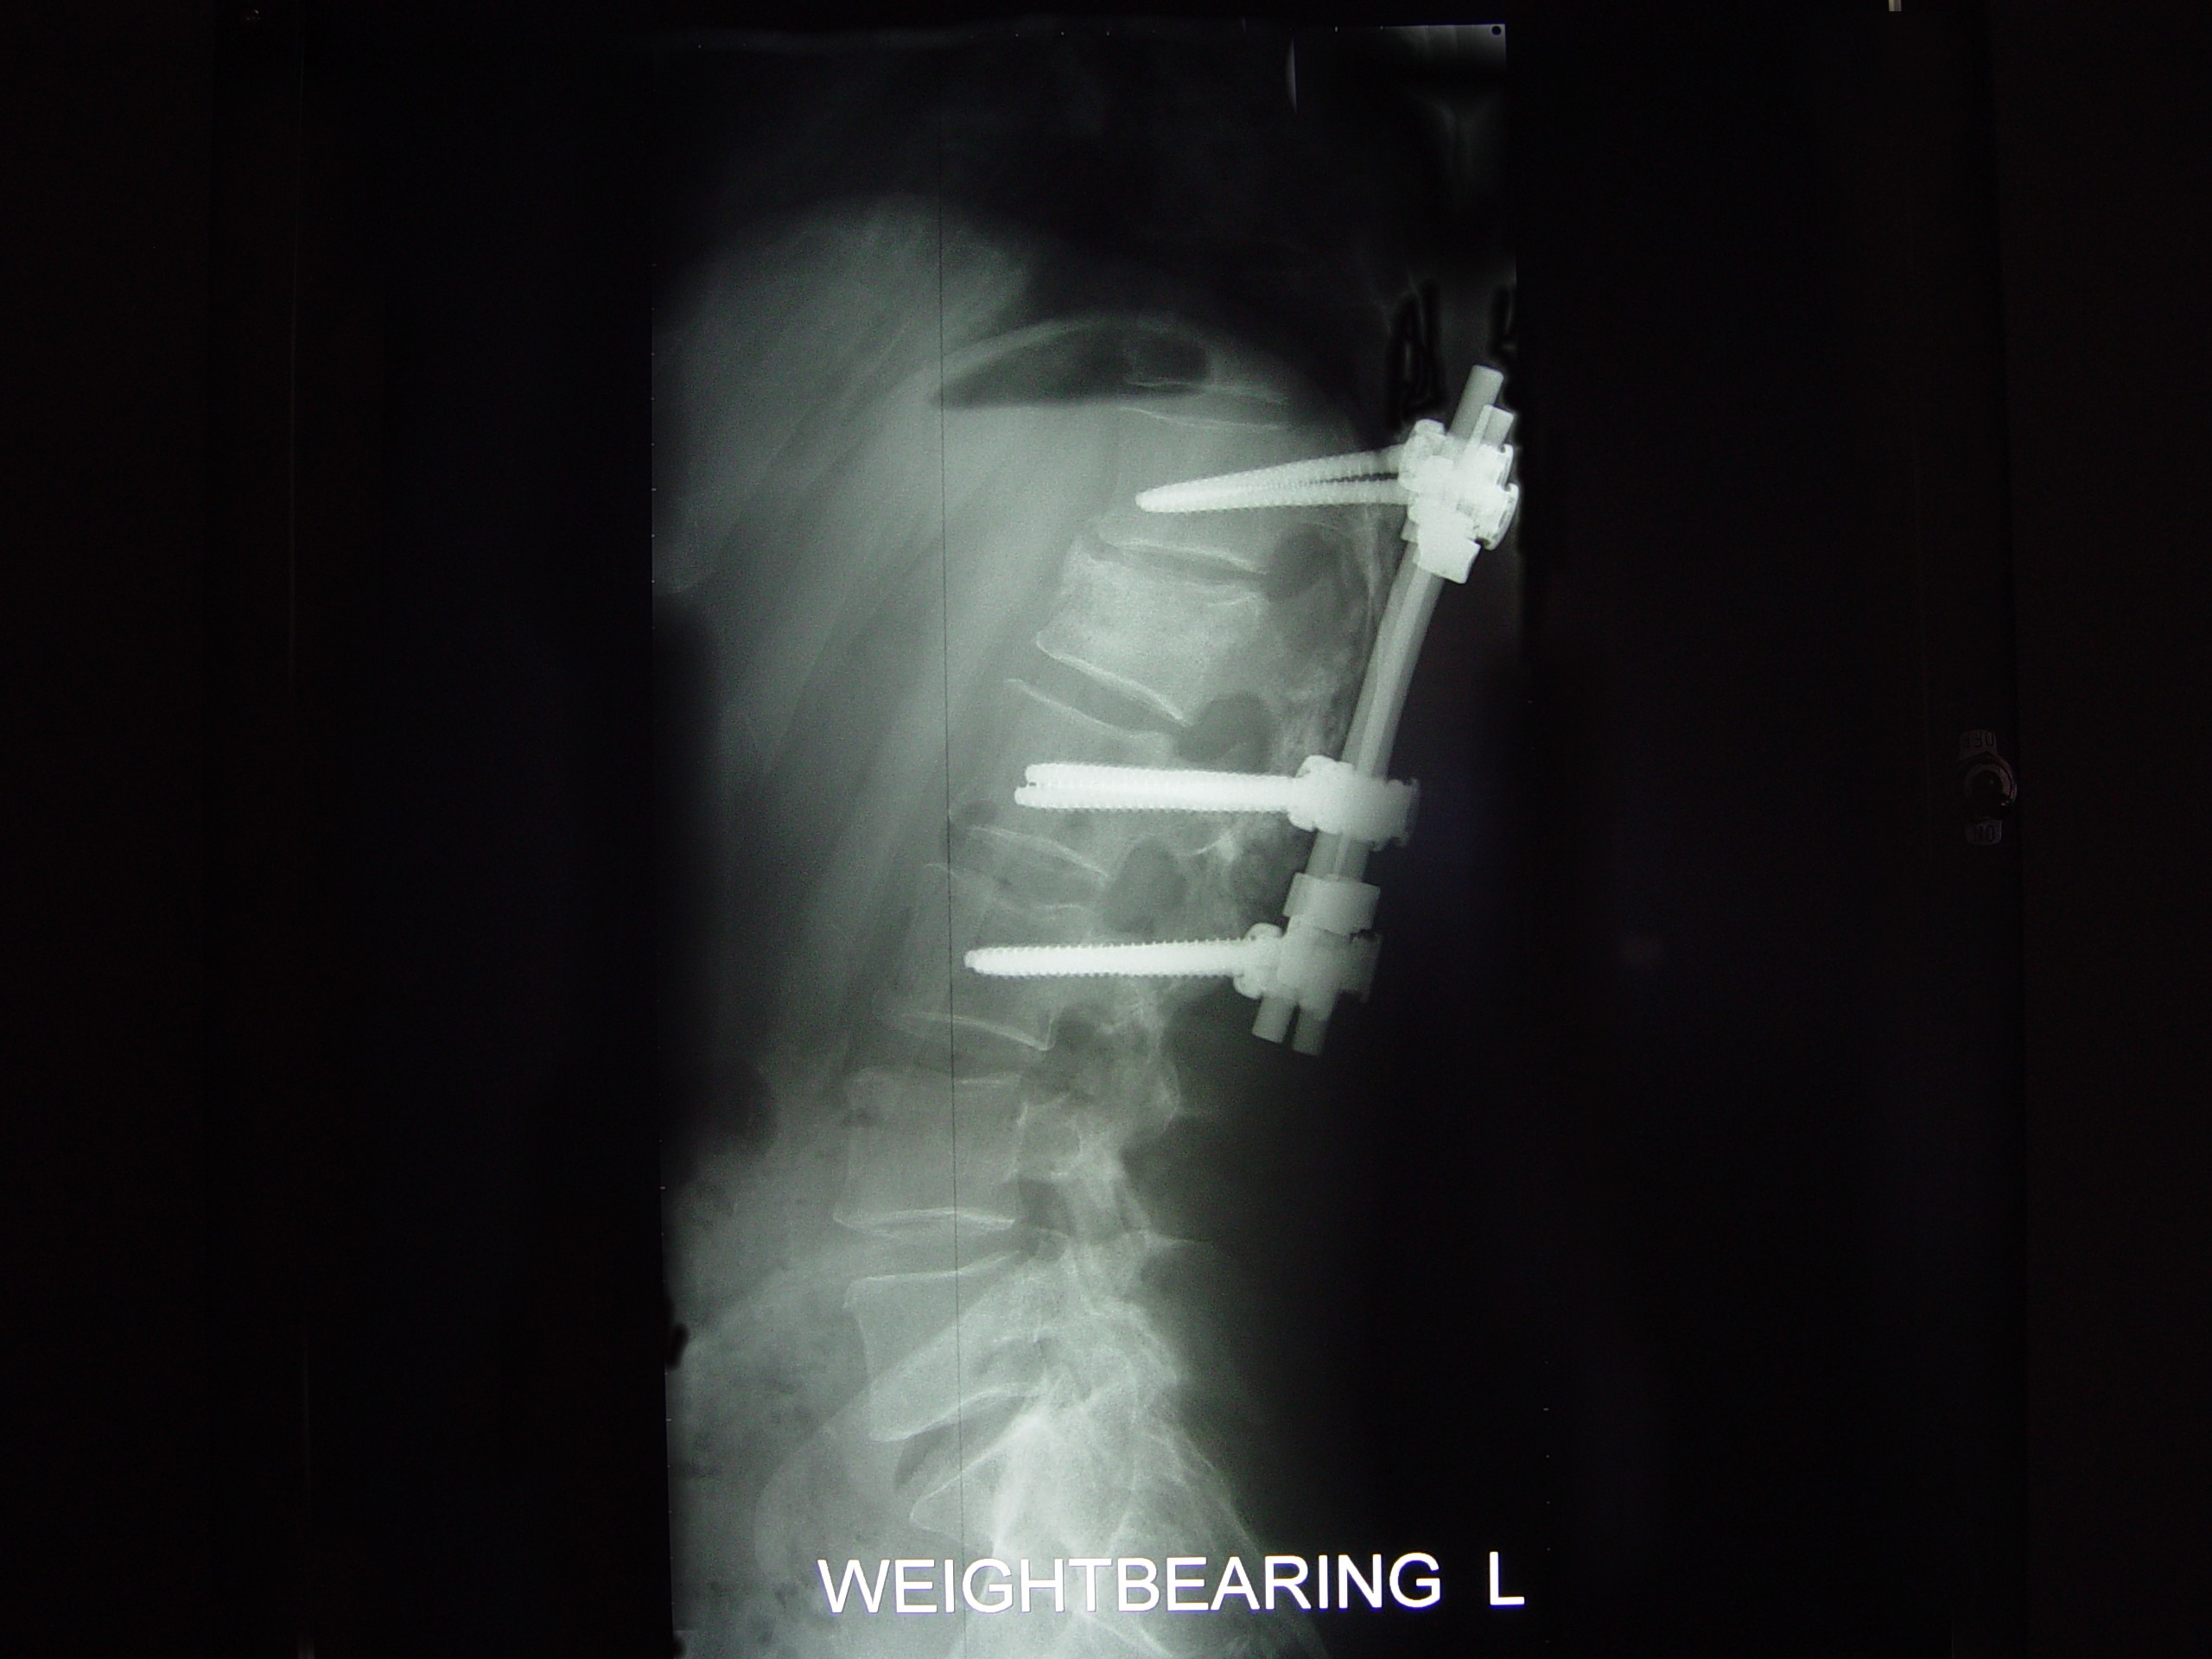

He has TWO rods in his back for support up and down... Two screws at the bottom of each rod and one at the top... He is in recovery at this time more than likely still...

He Faces a LONG three to Four months of bed rest while his back heals up... The Best of luck in all of this. The Doctors were able to do ALL of the surgery through his THIN little body Via his BACK and Did not have to cut his chest etc at all... He has 2 rods in his back and that is NOW confirmed and what I posted last night late is all good...

The hardware is coming out! On April 28th I'm gettin' this monkey off (out of) my back. Hopefully it is the source of the leg pain that has slowed the recovery process.

DSC09489.JPG

The Monkey: Side View